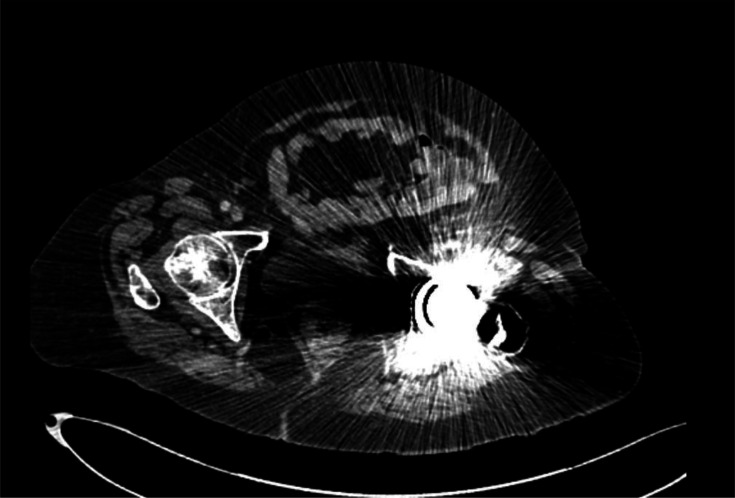

艰难梭菌(以前称为艰难梭菌)是卫生保健相关感染的一个重要原因,其症状从腹泻和腹痛到假膜性结肠炎和中毒性巨结肠。严重疾病可造成严重的发病率和死亡率风险,应被视为医疗紧急情况。一种新的艰难梭菌核型(995核型)的出现,估计死亡率为20%,促使人们重新审查有关处理严重艰难梭菌感染(CDI)的证据和指南。关于CDI管理的国际指南在一线抗生素选择方面各不相同。由于对耐药性的担忧,甲硝唑不再被推荐作为一线药物,万古霉素和非达霉素现在被推荐作为一线药物。抗生素治疗应结合良好的支持措施和早期考虑手术治疗。粪便微生物群移植可用于复发性CDI,并可用于严重疾病。严重的CDI是对公共卫生的重大持续威胁,进一步研究有效的管理对于确保患者获得最佳可能结果至关重要。

Clostridioides difficile (formerly known as Clostridium difficile) is a significant cause of healthcare-associated infection with symptoms ranging from diarrhoea and abdominal pain to pseudomembranous colitis and toxic megacolon. Severe disease can pose a significant morbidity and mortality risk and is to be considered a medical emergency. The emergence of a new C. difficile ribotype with an estimated mortality rate of 20% (ribotype 995) has prompted a re-review of the evidence and guidelines around managing severe C. difficile infections (CDI). International guidance on the management of CDI varies regarding first-line antibiotic choice. Metronidazole is no longer favoured as first line due to concerns around resistance, and vancomycin and fidaxomicin are now recommended as first line options. Antibiotic therapy should be used in conjunction with good supportive measures and early consideration of surgical management. Faecal microbiota transplant can be utilized in recurrent CDI and may be useful in severe disease. Severe CDI is a significant ongoing threat to public health, and further research into effective management is essential to ensure the best possible outcomes for patients.